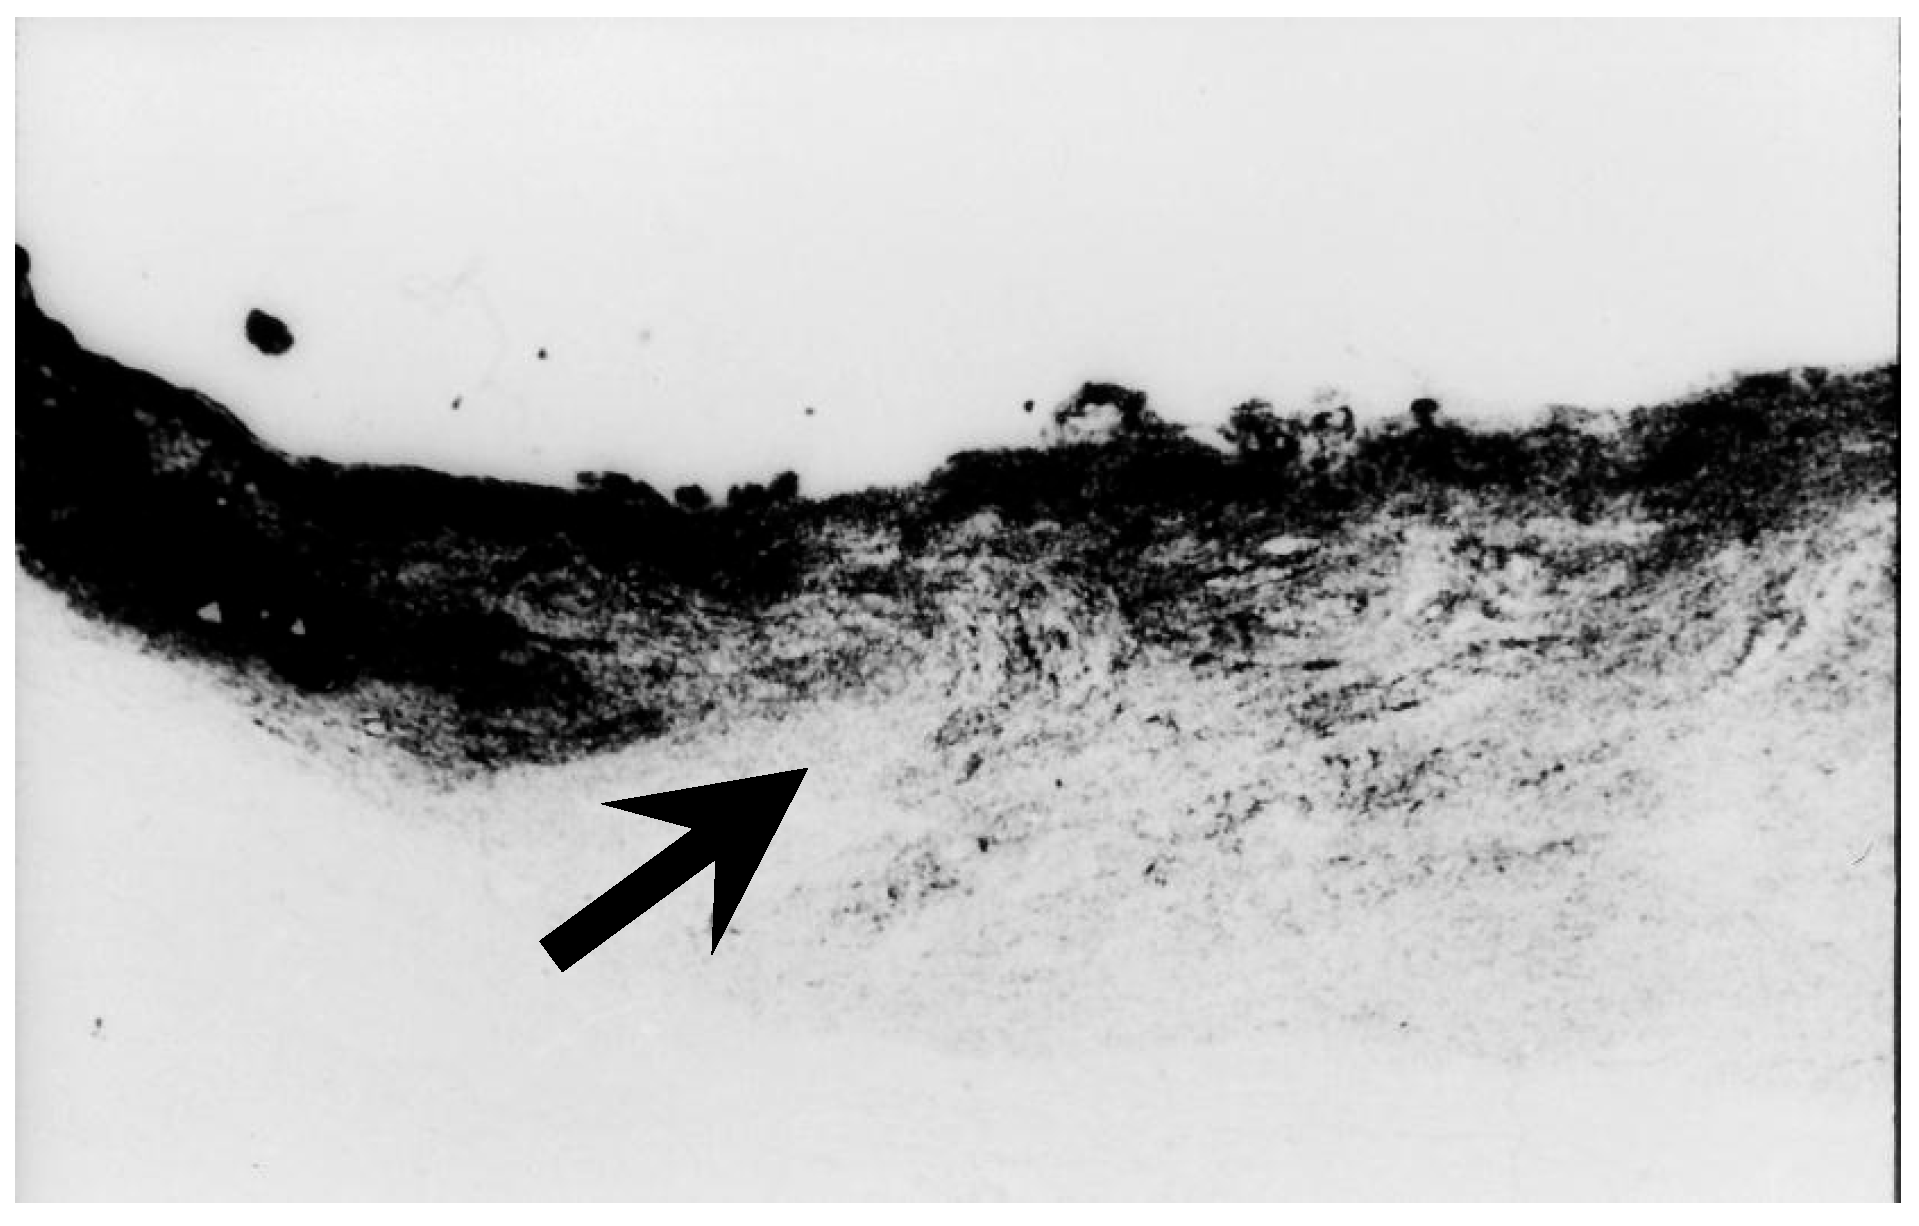

- Chihara, E.; Honda, Y. Preservation of nerve fiber layer by retinal vessels in glaucoma. Ophthalmology 1992, 99, 208–214. [Google Scholar] [CrossRef]

- Chihara, E.; Chihara, K. Apparent cleavage of the retinal nerve fiber layer in asymptomatic eyes with high myopia. Graefes Arch. Clin. Exp. Ophthalmol. 1992, 230, 416–420. [Google Scholar] [CrossRef]